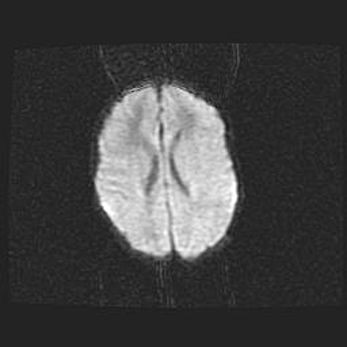

Наружная гидроцефалия с возможной атрофией височных областей.

Возраст: 28 дней

Вес: 3670 г

Пол: мужской

Окружность головы: 38 см

Срок гестации: 40 недель

Гидроцефалия головного мозга у новорожденных – это заболевание, которое характеризуется скоплением избыточного количества спинномозговой жидкости в желудочковой системе головного мозга в результате затруднения её перемещения от места выработки к месту поглощения в кровеносную систему или вследствие нарушения абсорбции. При открытой наружной форме гидроцефалии у новорожденных расширяются и переполняются субарахноидные пространства.

При нормотензивных  формах,  которые,  как  правило,  являются  следствием  перенесенных ишемических  повреждений  паренхимы  мозга,  возможно  сочетание микроцефалии  с нормотензивной гидроцефалией. В основе данных изменений лежит атрофия больших полушарий с преимущественной  локализацией  в  лобно-височных  областях.